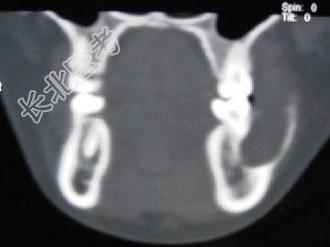

- 单项选择题男,28岁, 无意中发现左下颌骨较对侧隆起,CT如图所示, 最可能的诊断是 ( )

A、下颌骨齿釉细胞瘤

B、下颌骨巨细胞瘤

C、下颌骨角化囊肿

D、下颌骨根端囊肿

E、下颌骨含牙囊肿